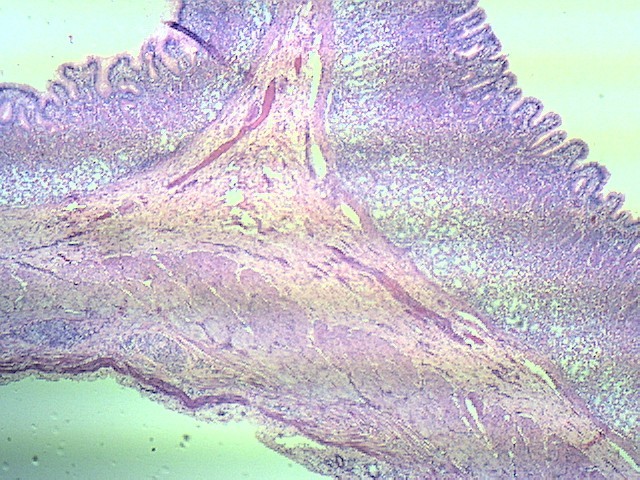

Ткани желудка - 3 шт.